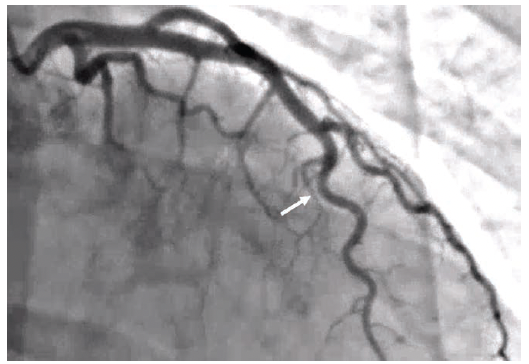

Patient 1 is a woman in her 50s, with chronic back pain, hypertension, and remote history of a transient ischemic attack (TIA). She presented to the emergency department with chest pain and elevated high sensitivity troponins >80,000 and was taken to the cath lab. She was found to have type II spontaneous coronary artery dissection in the mid to distal left anterior descending (LAD) coronary artery (Figures 1-2; Video 1). The right coronary artery (RCA) was normal. Of note, the patient had a similar presentation more than 1 year ago with high sensitivity troponins >16,000. The angiogram was normal (Figure 3; Video 2).